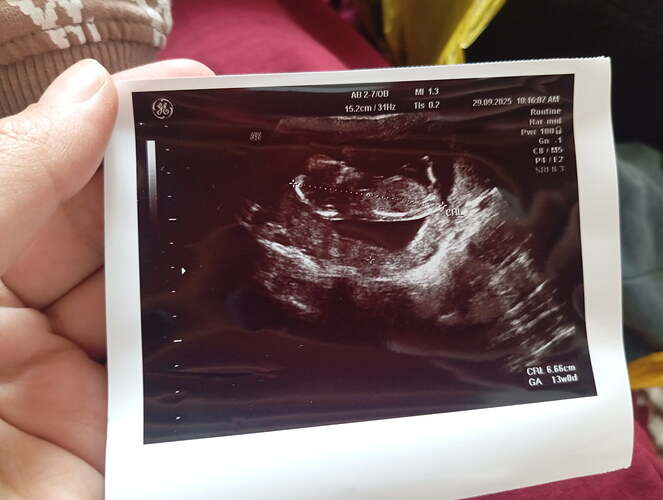

Sizce ney ![]()

![]()

Kese sekli gozukmuyor ki yakından kafa gozukuyor sadece. Uzaktan var mi